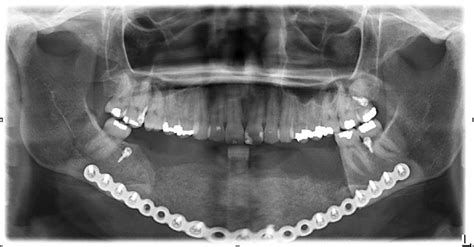

Seguidamente, el implante se coloca en el lecho quirúrgico. En caso de que exista una placa cortical gruesa, estará indicado el uso de una fresa avellanadora. Una vez el implante se ha asentado (figura 5) se conecta un pilar de cicatrización al implante y se obtiene de esta manera un cierre primario. En las figuras 6 y 7 se muestra el aumento de volumen óseo alcanzado.

El presente estudio clínico presenta los hallazgos clínicos y radiológicos del tratamiento del maxilar posterior con implantes insertados mediante la técnica de elevación transalveolar del seno maxilar.

En el presente estudio a 5 años, se ha utilizado implantes de 10-12 mm de longitud en unas localizaciones maxilares con una altura de hueso residual de 6,38 ±1,10 mm (rango: 5-10 mm).

Los resultados clínicos del presente estudio demuestran una elevada tasa de éxito (96,4%) de los implantes insertados mediante la técnica MISE de elevación indirecta o transalveolar del seno maxilar, con una ganancia ósea mantenida, para un periodo de seguimiento medio superior a los 5 años.

La altura ósea residual media fué de 6,38 ±1,10 mm (rango:5-10 mm). La ganancia media de hueso vertical fué de 4,40 ±1,15 mm (rango: 2-7 mm). 67,8% de los implantes se insertaron en localización molar y el 32,2% en la localización premolar. Se utilizaron biomateriales en el 97,8% de los implantes.